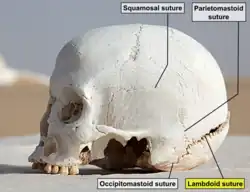

Lambdoid suture (labeled at bottom right) | |

The lambdoid suture (or lambdoidal suture) is a dense, fibrous connective tissue joint on the posterior aspect of the skull that connects the parietal bones with the occipital bone. It is continuous with the occipitomastoid suture.

The lambdoid suture is between the paired parietal bones and the occipital bone of the skull. It runs from the asterion on each side.

The lambdoid suture is named due to its uppercase lambda-like shape.